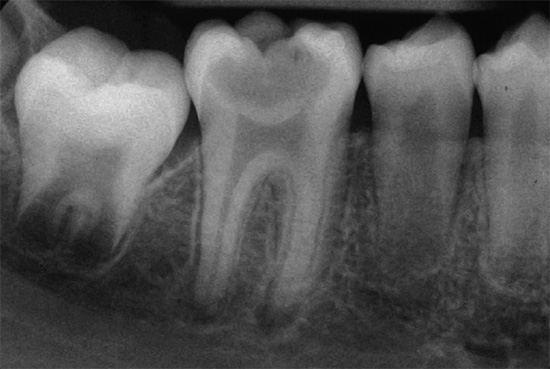

La radiografia è un metodo basato sullo studio di fotografie radiografiche di un dente con i tessuti circostanti trasferiti su un computer mediante un apparato - un visiografo (a meno che, ovviamente, non stiamo parlando di una clinica moderna).

Per confermare la diagnosi di pulpite ipertrofica cronica, la radiografia non dovrebbe mostrare alcun cambiamento nei tessuti che circondano il dente e nell'area del setto interropo. In un quadro dentale con pulpite fibrosa cronica, il più delle volte non ci sono anche cambiamenti, ma a volte viene fissata una leggera espansione del gap parodontale (tra la radice del dente e l'incavo), che complica la diagnosi. La polpite gangrenosa cronica è caratterizzata in rari casi da disturbi ossei all'apice delle radici dei denti, pertanto la diagnosi è confermata dalla termometria e dall'EDI.